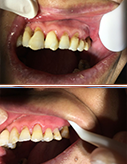

口腔种植

真实案例